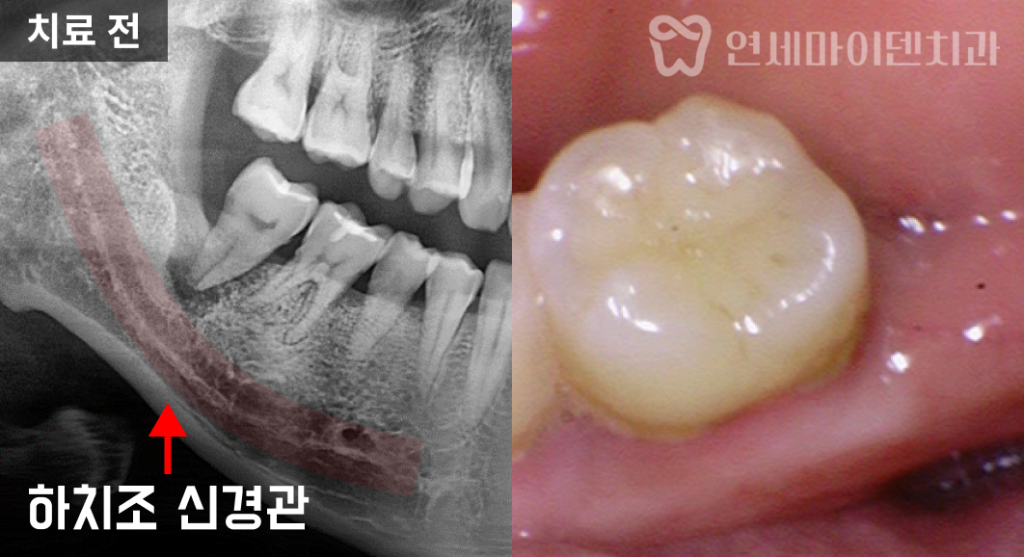

문제는 발치를 하더라도

하치조 신경관과 너무 가까운 위치이기 때문에임플란트를 심기 어렵다는 진단을

타원에서 받으신 겁니다.실제 엑스레이 상으로도

치아 뿌리 주변의 치조골이 까맣게 소실돼 있었고,신경관이 바로 인접해 보이는 모습이 관찰되었습니다.

엑스레이는 2차원적인 단면 영상이기 때문에

치조골 상태를 입체적으로 파악하기에는 한계가 있습니다.정확한 진단을 위해 3D 네비게이션 CT 촬영을 진행했습니다.

입체적 영상으로 확인한 결과,

입 안쪽 잇몸뼈는 많이 소실돼 있었지만

치조골 외측에는 하얗게 뼈가 남아있는 부분이 존재했습니다.단면 영상으로는 전혀 식립 공간이 없는 것으로 보였지만,

실제로는 바깥쪽 잇몸뼈가 충분히 남아 있었던 것입니다.또한 하치조 신경관과의 거리도 확보할 수 있어서

임플란트 식립이 가능한 상태임을 확인할 수 있었습니다.따라서 발치 즉시 임플란트 식립을 진행하기로 하였습니다.